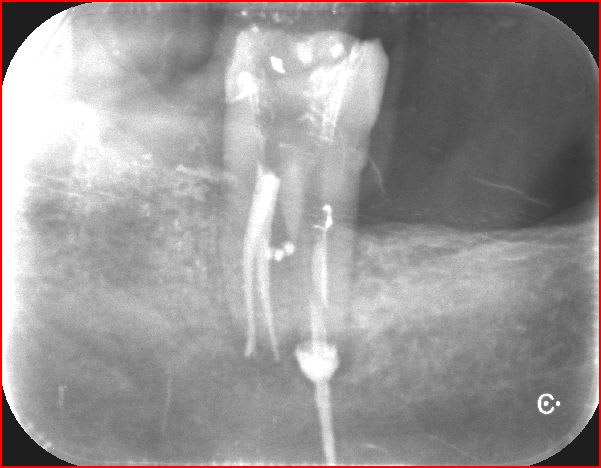

37

apres une endo de sauvage ,bien bourrée au compactor , 1 petit aller retour pour cette 37 .

pratique pour detartrer la face distale :-))

je vous tiens au courant .